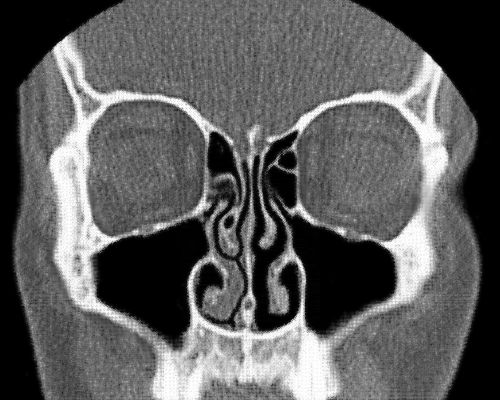

鼻循环 CT 扫描图,左侧有些肿胀堵塞,右侧通气顺畅。图片来源:Wikipedia